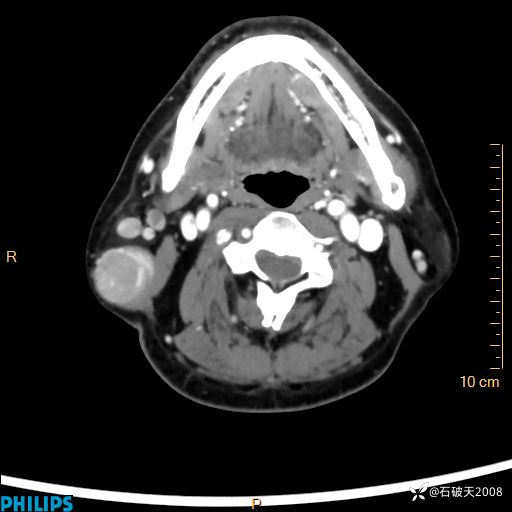

病例分享:颈部占位,一周后公布病理

男 57岁 主 诉:发现右侧颌下肿物1月余。

现病史:1月余前家属发现右侧颌下肿物。局部皮肤无红肿、热痛,无吞咽困难,无异物感,无恶心、呕吐,无头痛、头晕,无胸闷、胸痛,无发热、咳嗽、咳痰及呼吸困难。于我院行体表肿块彩超检查(2024.03.15我院)示:右侧耳下皮下软组织内低回声,未治疗。今为进一步治疗门诊以“腮腺肿瘤”为诊断收住我科,发病来患者神志清,精神可,饮食、睡眠及大小便正常,体重无明显下降。

动脉期